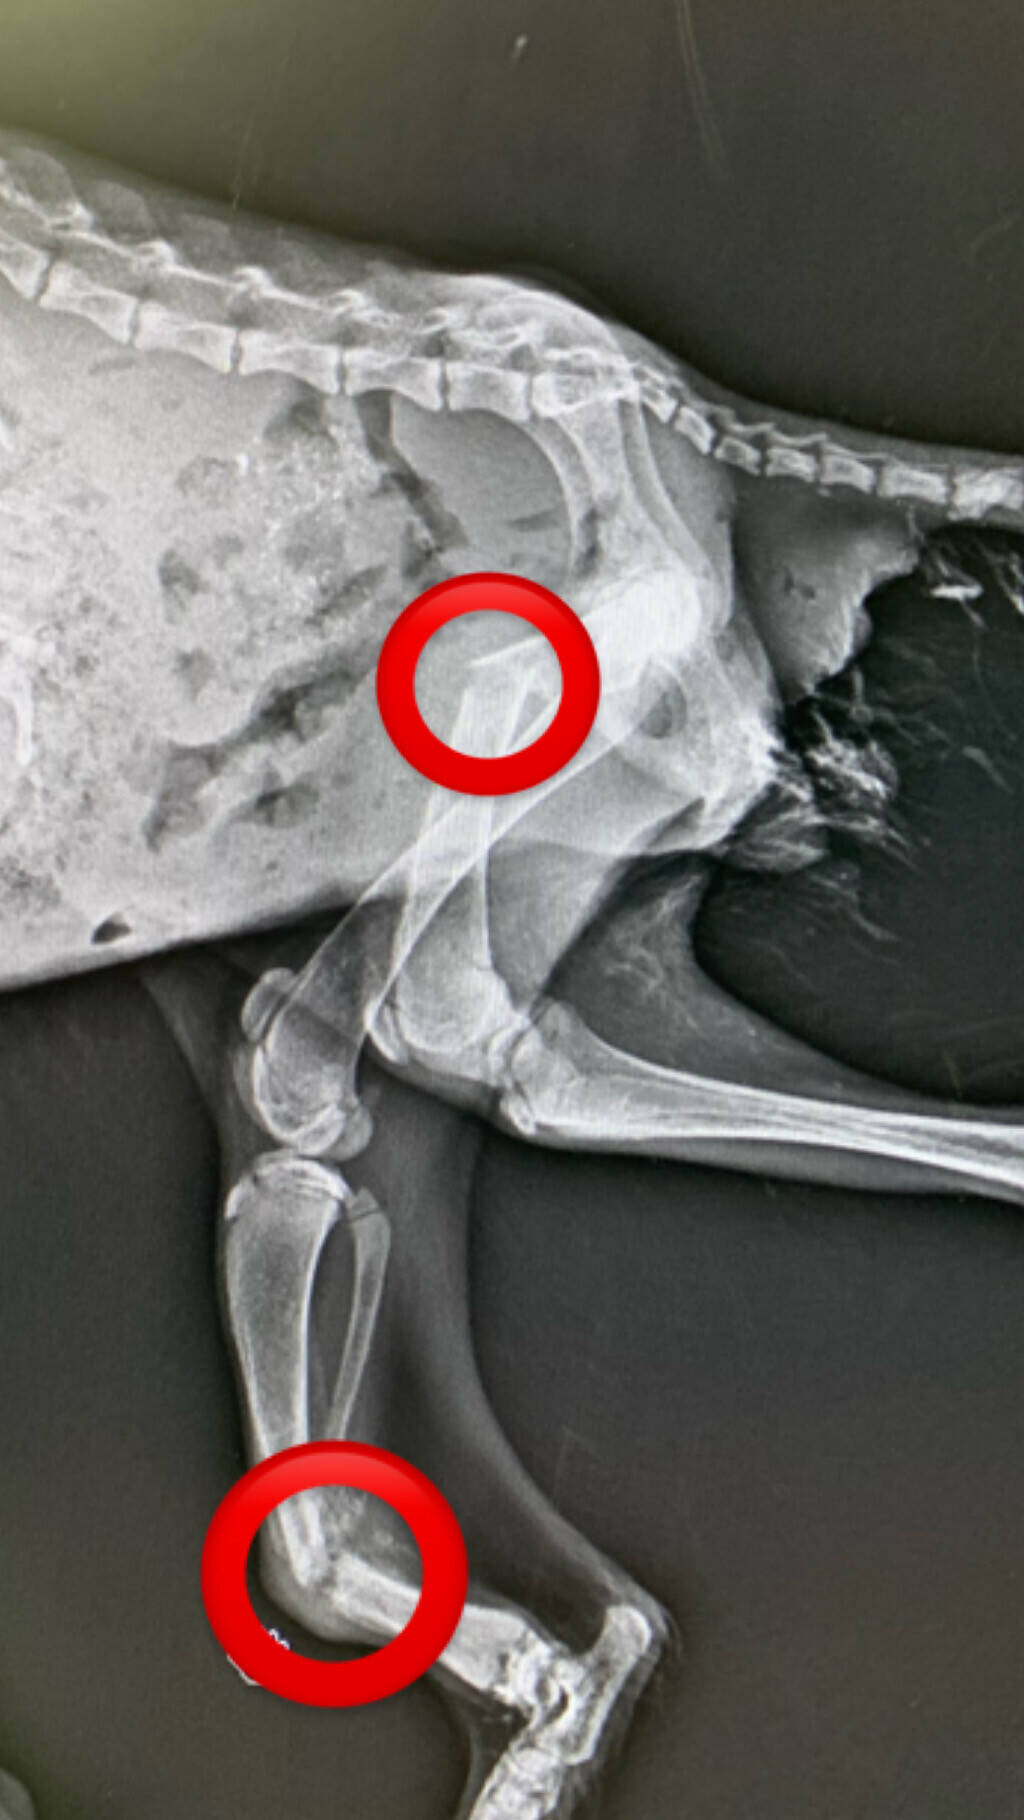

先日運ばれてきた「くる病」のタヌキのレントゲンです。↓

後肢の拡大図です。↓

ぼっきり折れているのがご覧いただけると思います。